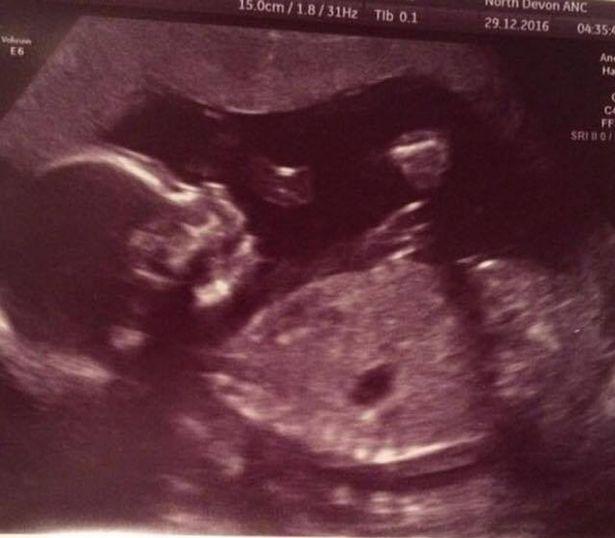

Αυτό συνέβη παρά την απώλεια που βίωσε, όταν η μητέρα της, η Michelle Nott πέθανε ξαφνικά, σε ηλικία 54 ετών, από καρδιακή προσβολή, λίγο μετά τον υπέρηχο των 20 εβδομάδων της, τον Δεκέμβριο του 2016.

“Είχε έρθει στον υπέρηχο των 20 εβδομάδων μαζί μας λίγες μέρες νωρίτερα. Ήταν μια χαρά και ανυπομονούσε να καλωσορίσει ακόμη ένα εγγόνι. Τότε ”έφυγε” ξαφνικά.

Κατά την άφιξή της, μεταφέρθηκε αμέσως στην αίθουσα τοκετού, όπου της έγινε υπέρηχος και ανακάλυψαν οτι ο πλακούντας της είχε αποκολληθεί εξ ολοκλήρου. Αλλά τα συμπτώματα ήταν σε μεγάλο βαθμό δεν υπήρχαν οπότε δεν είχε συνειδητοποιήσει ότι κάτι δεν πήγαινε καλά μέχρι που άρχισε ο πόνος.